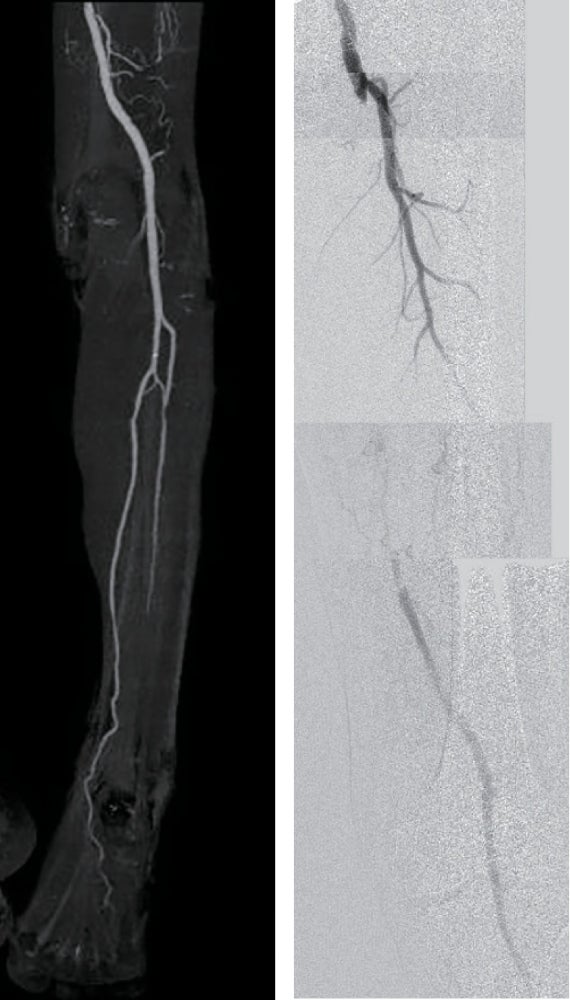

- IVUSにて遠位部のヘルシーな部分をマーキングし、バイアバーン® ステントグラフト径6.0/長250 mm を留置(図2)。

- 径6.0/長150 mm高圧バルーンにてP3 segmentの穿刺部止血を兼ね長時間拡張し、バイアバーン® ステントグラフト内を高圧拡張。

- 造影上は良好な血流改善を得られたが、IVUSではSFA起始部にプラーク残存を認めた(図3)。